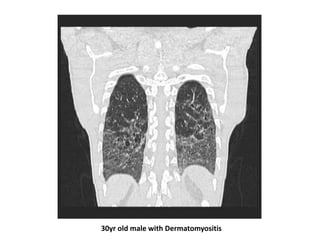

DM/PM-ILDs

• Radiographic and pathologic findings in patients with ILD

secondary to DM/PM are the most varied of all the CTD-

ILD

• Radiographic study of patients with DM/PM showed that

all patients with fatal ILD had ground glass opacities on

HRCT scan, with consolidation being the principal finding in

most nonfatal cases

• Poor outcome was associated with a rapidly progressive

respiratory failure and DM-ILDs

30yr old male with Dermatomyositis